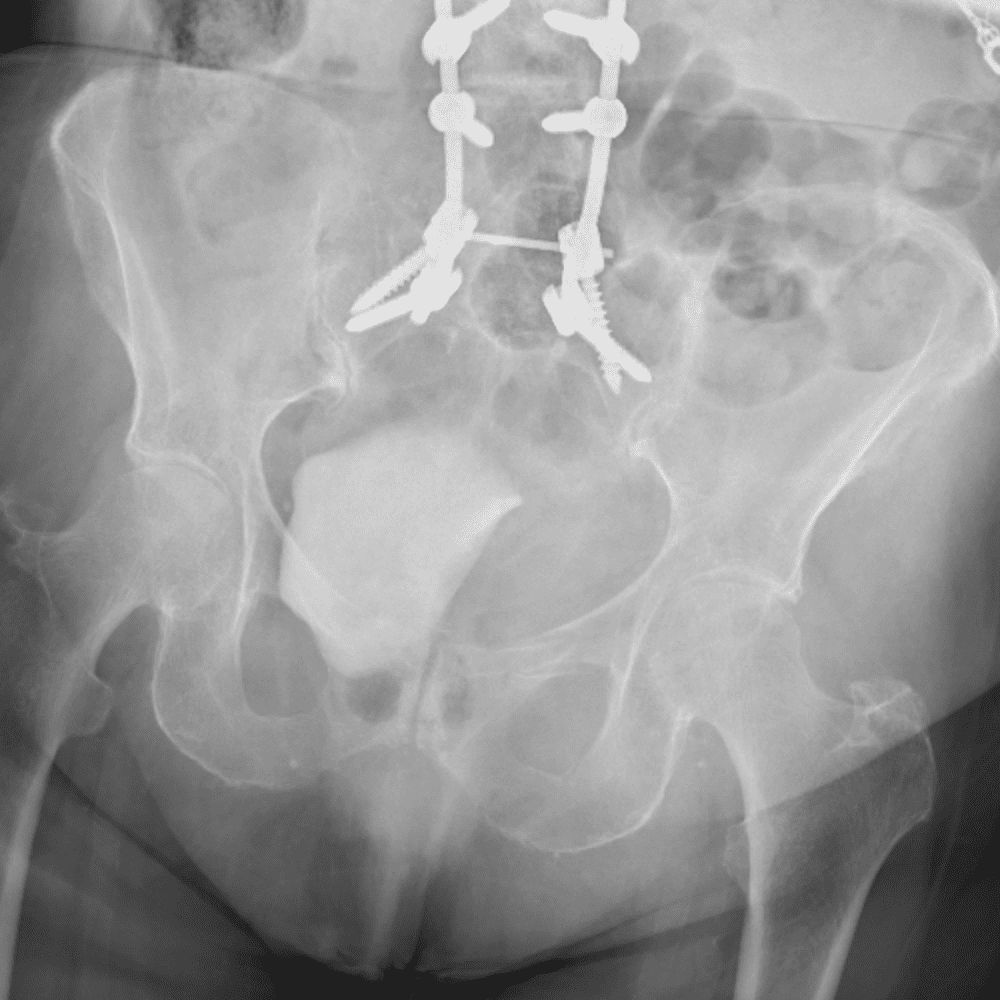

通过包含微妙或困难的病例和一些正常病例来模拟值班。